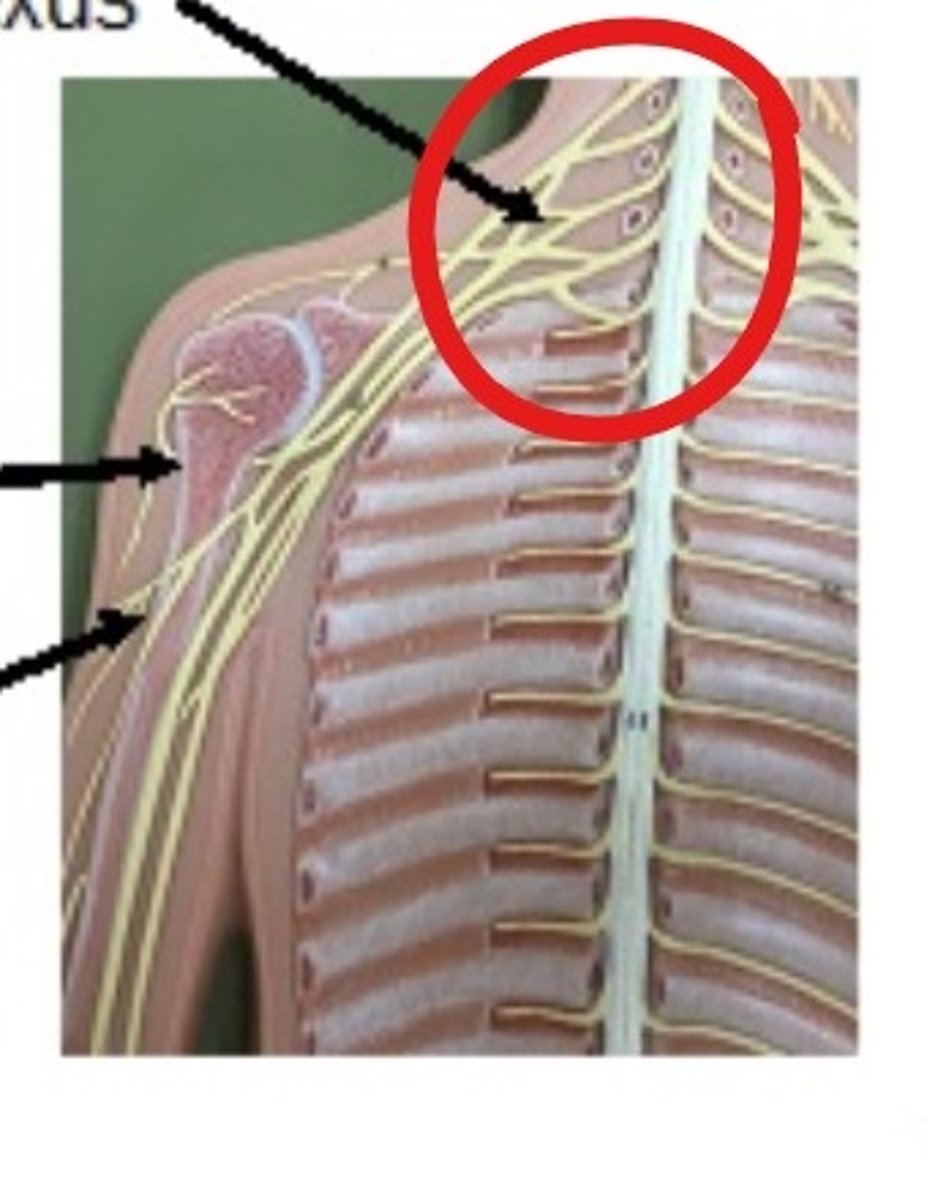

brachial plexis

6000 cGy (whole)

td5/5 for brachial plexus

can cause neuropathy (numb and tingling down the hands)

what can happen if brachial plexius is over eradiated (more then td55 of 6000cGy)